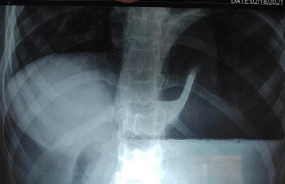

Water-soluble gastrografin meal showing postoperative normal positioning of stomach (Courtesy Dr. V. Penopoulos)